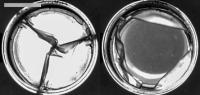

This prototype of an expanding artificial heart valve could make a big dent in the number of surgeries that many kids born with congenital heart disease need.

The latest prototype from the team is built from a biocompatible polyurethane that closely matches the stretchiness of natural heart valves. To increase the size of the valve, a balloon catheter is inflated within the valve. “Because the polymeric material can deform permanently, the valve stretches and then remains at that new larger size to accommodate the growing child—until it needs to be stretched again,” Kysar says.

Photo courtesy of Abby Herschman, a PhD candidate in the Kysar lab who researches the material properties of the polymer used in the prototypes.